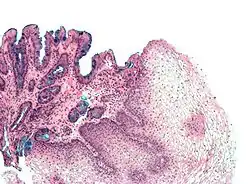

[Micrograph] of normal stratified squamous epithelium and the metaplasic epithelium of Barrett's esophagus (left of image). Alcian blue stain.